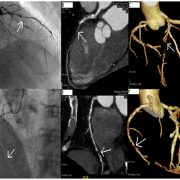

LimFlow Announces Positive Six-Month Data From Promise I U.S. Early Feasibility Study – Cath Lab Digest

Interesting new technology—early feasibility data for the LimFlow system for the teatment of chronic limb-threatening ischemia is positive, with the novel approach showing an encouraging amputation-free survival rate of 74 percent and 100 percent of wounds classified as healed or healing at nine months follow-up. “The minimally-invasive LimFlow system is designed to bypass blocked arteries in the leg and delivery oxygenated blood back into the foot via the veins,” reads the press release. Read more »